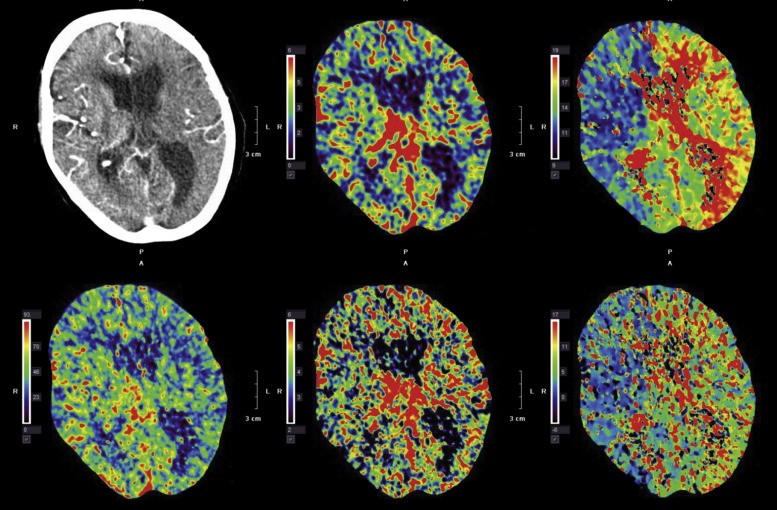

دو روش اصلی برای تصویربرداری پرفیوژن ایجاد شده است: روشهایی که با استفاده از ماده حاجب برونزا و بدون آن استفاده می شوند. گروه اول تکنیک ها شامل کنتراست حساسیت دینامیک MRI(DSC) و کنتراست دینامیک MRI(DCE) است. در حالی که گروه دوم به برچسب گذاری اسپین شریانی (ASL) مربوط می شود. DSC-MRI فقط در مغز برای ارزیابی بالینی پرفیوژن در ایسکمی مغزی و تومورهای مغزی استفاده می شود. این روش شامل تزریق سریع وریدی ماده حاجب رزونانس مغناطیسی و اندازه گیری سریال از دست دادن سیگنال در حین عبور بولوس از بافت ، با استفاده از تصاویر وزن دار T2 یا T2* است. DCE-MRIیکی دیگر از روشهای تصویربرداری پرفیوژن است که متکی به تزریق ماده حاجب است ، اما در آنجا تصاویر رزونانس مغناطیسی با وزن T1 به صورت دینامیک قبل ، حین و بعد از تزریق بولوس ماده حاجب بدست می آیند. داده ها را می توان از نظر مشخصات فیزیولوژیکی بافت با استفاده از اصول فیزیکی مدل سازی ردیاب-جنبشی تفسیر کرد. این روش در بسیاری از برنامه ها استاندارد شده است. در مقابل ، ASL یک روش تصویربرداری پرفیوژن برای اندازه گیری کمی پرفیوژن مغزی است که از آن به عنوان جریان خون مغزی (CBF)، با بهره گیری از استفاده از خون دارای برچسب مغناطیسی به عنوان یک ردیاب درون زا نیز یاد می شود. ASL به طور گسترده ای در صحنه تحقیق انجام شده و به طور پراکنده در بیماری ها اعمال می شود.

روش های تصویربرداری پرفیوژن مبتنی بر کنتراست برای گرفتن عبور بولوس به رزولوشن زمانی بالایی نیاز دارند ، به ویژه هنگامی که بیشتر ماده حاجب داخل عروقی باقی بماند. روشهای تصویربرداری پرفیوژن ، تخمین چندین پارامتر مهم همودینامیکی را هم شامل می شود که شامل جریان خون ، حجم خون و میانگین زمان عبور (MTT) است. تاکنون ، عمده ترین کاربردها در ارزیابی و مدیریت بیماران مبتلا به سکته مغزی حاد و تومورها بوده است. اندازه گیری نفوذ پذیری ماده حاجب ، مانند ثبات انتقال مربوط به سطح نفوذپذیری (Ktrans) و حجم کسری فضای خارج سلولی بدون رگ ، ممکن است برای ارزیابی بیماری های مختلف مفید باشد.

حساسیت دینامیکی – MRI یکی از روشهای مبتنی بر کنتراست است و به تزریق داخل وریدی ماده حاجب پارامغناطیس مانند مواردی که شامل کلات های گادولینیوم (Gd) است ، تکیه می کند تا یک بولوس کاملاً مشخص تولید کند. بیشتر کلات های Gd ، ردیاب محفظه خون غیر قابل دیفیوژن هستند. این روش با استفاده از تصویربرداری بسیار سریع اولین عبور ماده حاجب را نشان می دهد و از این رو به عنوان MRI ردیابی بولوس نیز شناخته می شود. این روش براساس تغییرات حساسیت پس از تزریق ماده حاجب است. ماده حاجب ماده پارامغناطیسی است که میدان مغناطیسی را تحریف می کند و T2 را در اطراف رگ به دلیل افزایش اثر حساسیت کاهش می دهد.